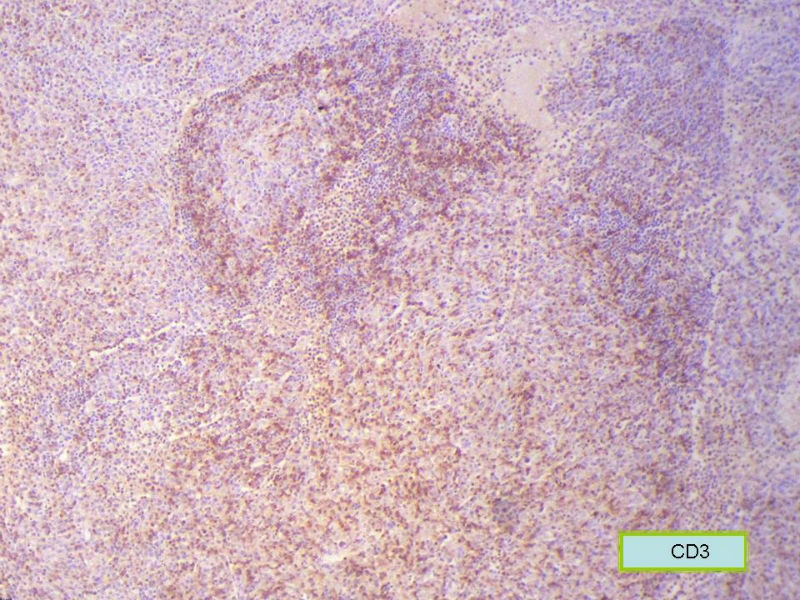

该患者可能存在病毒的感染,抑或是EB病毒的感染,包括CD30+的细胞在内,夹杂在组织细胞、小淋巴细胞之间的一些个大细胞是活化的淋巴细胞,表型看来属B细胞。整个形态呈反应性增生的形态。

标记树突细胞标志物CD21或CD23或D2-40,可能显示树突网与HE见到的明确的滤泡生发中心一致。

Ki-67标记在淋巴滤泡(生发中心)细胞全阳性,而且显示出生发中心边缘规则,不像是肿瘤,呈反应性增生。

Ki-67标记在滤泡间和淋巴组织弥漫增生区见散在阳性细胞,这些阳性细胞可能是转化性淋巴细胞,有的甚至是内皮细胞或组织细胞。

总之,现有的图片显示的形态和IHC标记尚不足以诊断为淋巴瘤,除非有有基因重排的支持。

请看下图,显示的细胞比较杂,胞浆较丰富,胞核没有什么特别的异型性。没有促纤维增生反应和围血管生长表现,没有肿瘤性坏死,没有见到更多的核分裂,特别是病理性核分裂。因此认为,本例是淋巴组织反应性增生,可能是对病毒感染的反应。